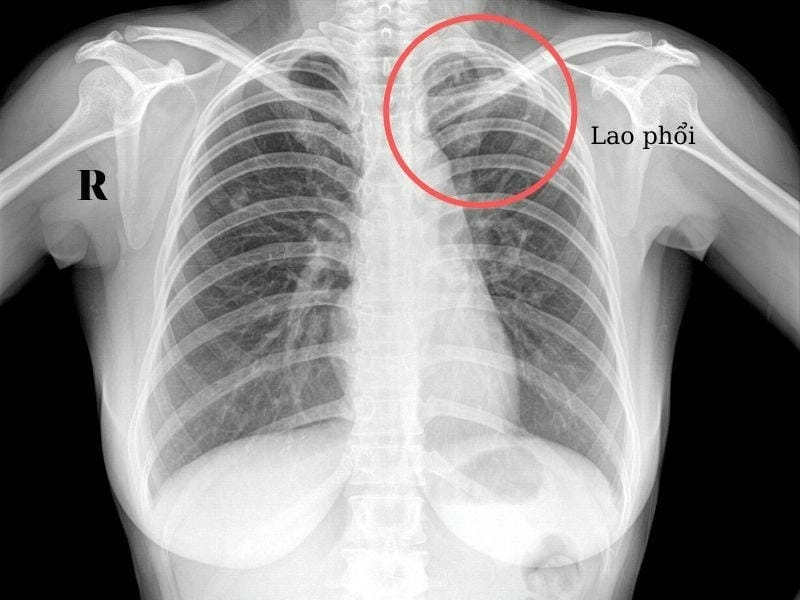

Hình ảnh bệnh lao phổi là tài liệu tham khảo quan trọng giúp người bệnh và bác sĩ dễ dàng nhận biết dấu hiệu bất thường. Việc quan sát hình ảnh X-quang, CT phổi giúp chẩn đoán chính xác mức độ tổn thương và đưa ra phương án điều trị kịp thời.

Bạn sẽ phải rùng mình khi chiêm ngưỡng hình ảnh bệnh lao phổi là như thế nào dưới ống kính y học thực tế. Những bức ảnh chụp X-quang cho thấy phổi bị tổn thương nặng, xuất hiện những đốm trắng mờ như bóng ma ám ảnh. Không chỉ là các tổn thương vật lý, đây còn là những “chứng tích sống” của căn bệnh âm thầm hủy hoại cơ thể qua từng hơi thở. Từ viêm nhẹ đến tổn thương lan rộng, hình ảnh bệnh lao phổi khiến người xem không thể rời mắt vì mức độ nghiêm trọng mà nó thể hiện rõ ràng qua từng chi tiết.

Tìm hiểu chi tiết hình ảnh lao phổi trên x quang